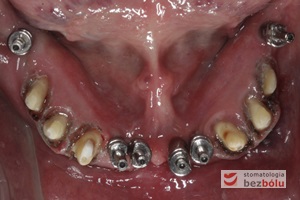

Transfery wyciskowe przykręcone do implantów - zęby własne opracowane jako filary pod korony całoceramiczne - skoagulowane dziąsła brzeżne

Transfery wyciskowe przykręcone do implantów – zęby własne opracowane jako filary pod korony całoceramiczne – skoagulowane dziąsła brzeżne

Wprowadzenie gotowych koron na zęby i implanty - śruby łączników tytanowych zamknięte różową gutaperką

Wprowadzenie gotowych koron na zęby i implanty – śruby łączników tytanowych zamknięte różową gutaperką